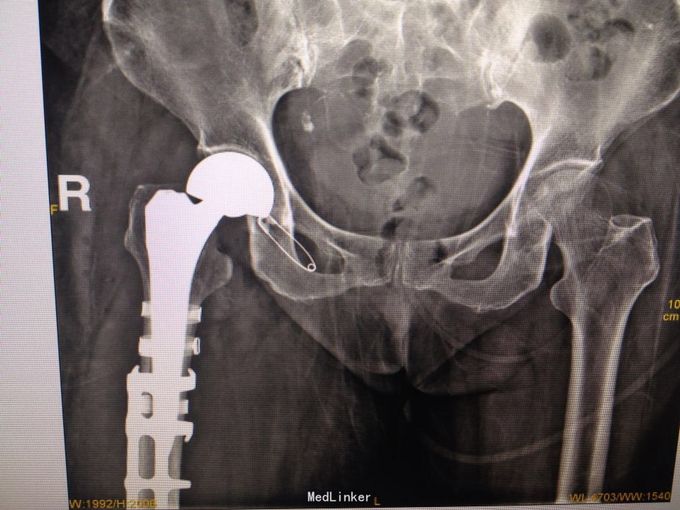

右股骨头置换术后股骨假体周围骨折(B3) 行右人工股骨头置换术后假体周围骨折切开复位记忆合金钢板+钛缆绑带固定术

术后3个月随访效果佳